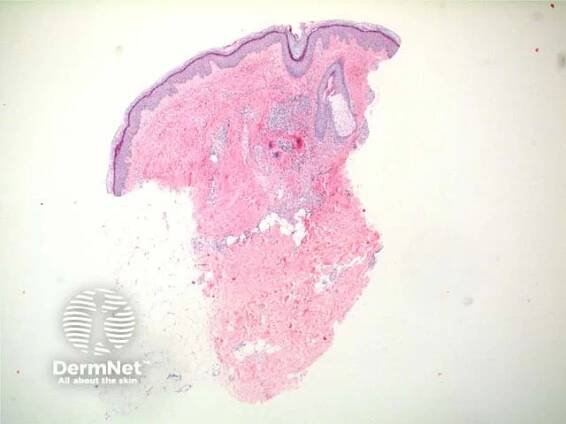

Cutaneous small-vessel vasculitis

Vasculitis leukocytoclastic (non-iga-associated)